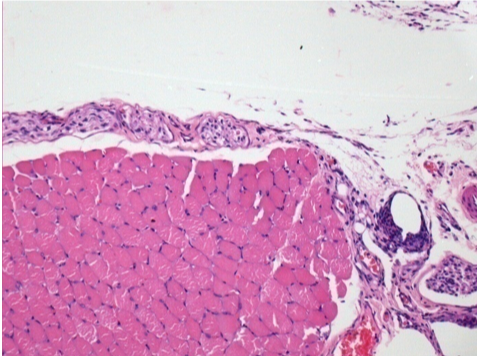

Через 10 днів після ін'єкції Ендопіл 0,1 мл в правий претибіальний м'яз.

Тут можна побачити утворення вакуолей, які оточені лімфоцитами. Вакуолі відрізняються від некрозу тканини. Присутність лімфоцитів пов'язана з проникністю клітинних мембран.